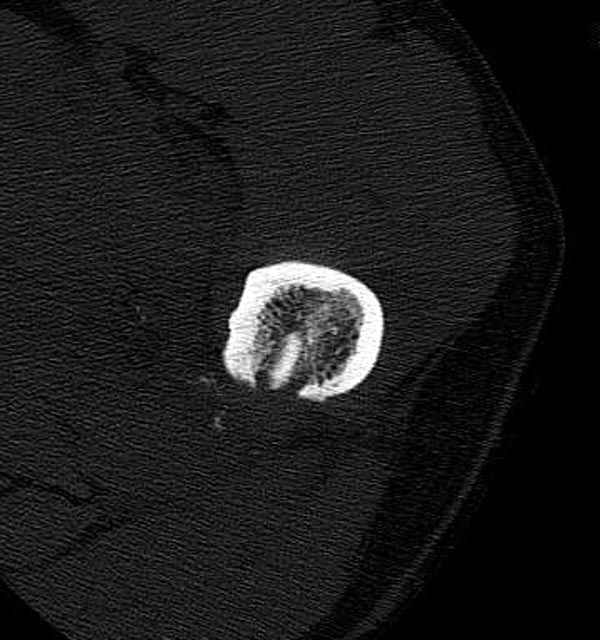

Больной с огнестрельным переломом бедра с вовлечением около 15% медиального кортекса, входное отверстие около 1 см в диаметре; стабильный, без сосудистых и неврологических признаков.

Литературные данные о влиянии кортикального дефекта на стрессовые переломы в длинных трубчатых костях в основном встречаются в онкологии, например кортикальный дефект более 50% имеет больше шанса стрессовых переломов, чем в нашем случае.

Учитывая, что больной получил травму не во время визита в церковь, и он является одним из представителем 40 миллионного “outstanding itizen”, без медицинской страховки, без работы в свои 39 лет, и без надлежающей ортопедической дисциплины у которого отсутсвует страх стрессового перелома, было рекомендовано оперативное лечение: профилактическое антеградное интрамедуллярное штифтование.

Методика штифтования при отсутствии большой зоны перелома как при онкологических профилактических штифтованиях, расверливание интрамедуллярного канала проводим с предварительным наложением дополнительного дренажного отверстия в дистальном отделе бедра (в данном случаи в канале оставили 6.5 мм канюлированный шуруп), иначе при создании давления в канале во время сверления имеется опасность эмболизации легочной артерии тромбом.